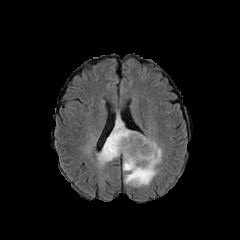

Refer to caption

(e) Normal Liver

(f) Normal Liver

(g) Liver Tumor

(h) Liver Tumor

Figure 4: We show some example brain MRI slices from BratS18 (first row) and Liver CT slices from LiTS (second row). Both normal- and abnormal-looking images are provided.

Aside from the difference in imaging tissue and modality of these two data sets, the tumor regions on the CT images are of different shape and size, as can be seen in Figure 4. Also, many CT scans are acquired in a way that introduces greater noise-like artifacts than MRI. For each dataset, 80%percent8080\% of randomly selected data are used for training and the resting 20%percent2020\% for testing.